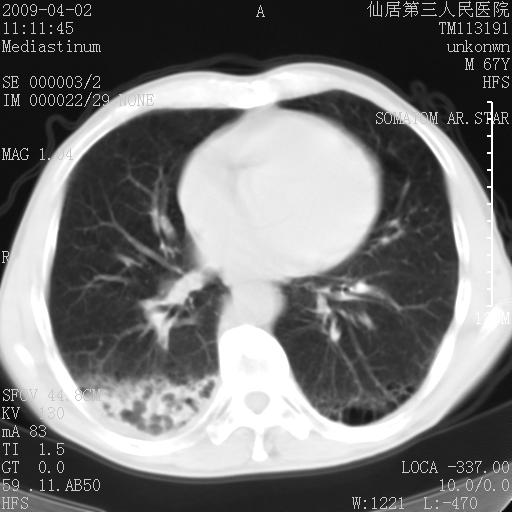

患者老年男性,乏力畏寒来诊,摄胸片示右下肺感染性病变,抗炎两周后复查胸片,无好转有进展。

后做ct平扫表现如下:

考虑右肺炎症可能性大,不除外细支气管肺泡癌

是否还要考虑肺间质纤维化,建议hrct扫描。

病灶呈蜂窝征,纵隔多个淋巴结肿大;肺泡癌需考虑

我认为普通的感染应该可以除外,间质性肺炎可能性较大,但如何解释纵膈的淋巴结肿大呢

考虑双肺间质性改变(间质纤维化?)伴右肺下叶感染。